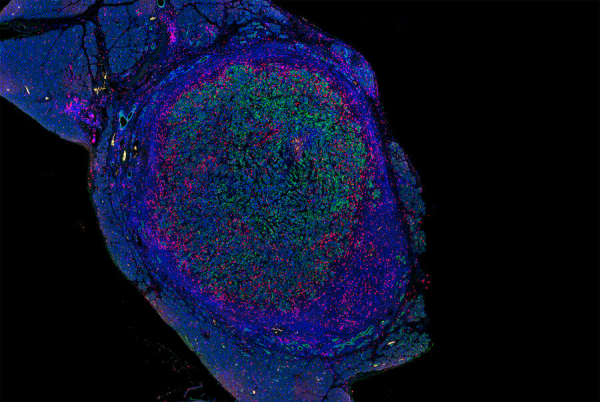

接受治疗后胰腺肿瘤中的T细胞(粉色)浸润了肿瘤细胞(绿色)图片来源:原文